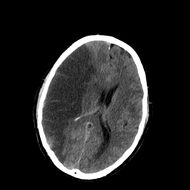

CT scan slice of the brain showing a right-hemispheric ischemic stroke (left side of image).

السكتة النزيفية Hemorrhagic stroke

CT scan showing an intracerebral hemorrhage.

سكتة نتيجة نزيف في المخ:

ويعني تجمع الدم في أي مكان ضمن الجمجمة ويظهر في صورة صداع ويكون نتيجة كدمة بالرأس

أو نزيف داخل المخ Intracerebral haemorrhage